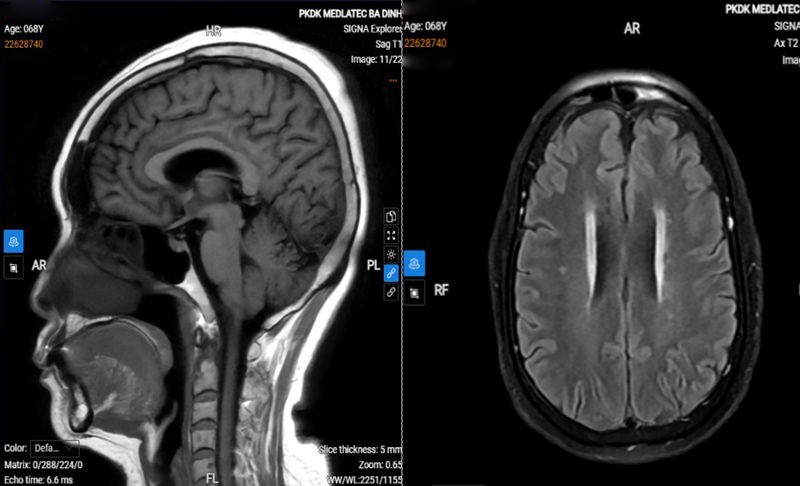

Kết quả chụp cộng hưởng từ (MRI) sọ não có dấu hiệu thoái hóa myelin chất trắng; siêu âm Doppler hệ động mạch cảnh và đốt sống đoạn ngoài sọ chưa phát hiện bất thường. Đo lưu huyết não ghi nhận giảm lưu lượng hệ động mạch đốt sống – thân nền bên trái. Các thăm dò tim mạch như điện tim và siêu âm tim trong giới hạn bình thường. Ngoài ra, siêu âm tuyến giáp phát hiện nang thùy phải; xét nghiệm máu thấy chỉ số đường máu và mỡ máu tăng cao.

Hình ảnh chụp MRI sọ não của bệnh nhân thấy có dấu hiệu thoái hóa myelin chất trắng